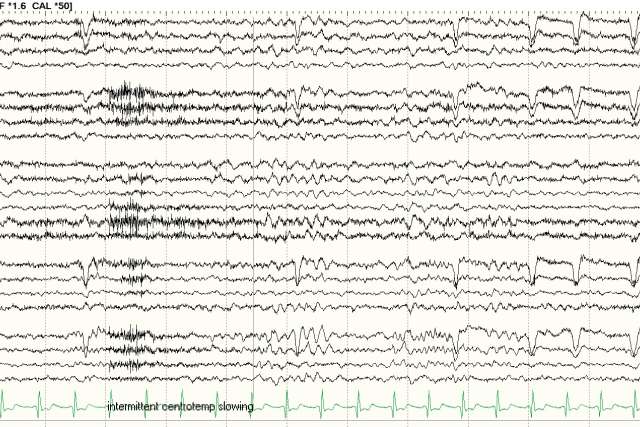

EEG from a 12-year-old boy who developed epilepsy throughout the observation period. “We found the presence of EEG slowing (shown around a vertical line) is highly correlated to the risk of epilepsy development,” explains Hiroki Narai, MD, PhD, MS, assistant professor of pediatrics, division of pediatric neurology, and medical director of the pediatric epilepsy surgery program at UCLA. (Image courtesy of Dr. Nariai)

This data is intriguing because we found the presence of EEG slowing ALSO predicts future development of epilepsy. We didn’t think that would be the case, but data showed exactly that. This likely signifies an underlying pathology, a brain network issue.